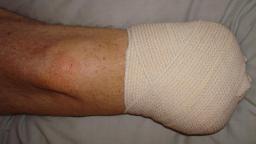

Postoperative (14th) images of left ankle

The image(s) displayed here were created following Liam's 14th surgery which was performed by Dr. Saunders. It was thought that the bones

in the ankle had fused, but during surgery it was discovered that the ankle was a total non-union. The halo frame was removed and 3 anchors were

placed on the tibia. Also added to the ankle was all available Medtronic Infuse material (rhBMP). One image may provide proof that Dr. Saunders

is possessed. ;-) The first set of x-ray shots were taken 3 weeks after the 14th surgery. The 3 new claw anchors are visible as seen through

the cast. Excess bone debris was also removed. Some of the photos had to be taking with the cell phone since the main camera failed. The last

x-rays show that some of the screws in the claw anchors are backing their way out of the leg. The next phone photos show that a screw from a

claw anchor was actually sticking out of the leg and could easily be removed (by hand) by the doctor. The very last photo is of the leg wrapped

in a black cast. Black was used to signify the loss that was soon going to occur. :-(